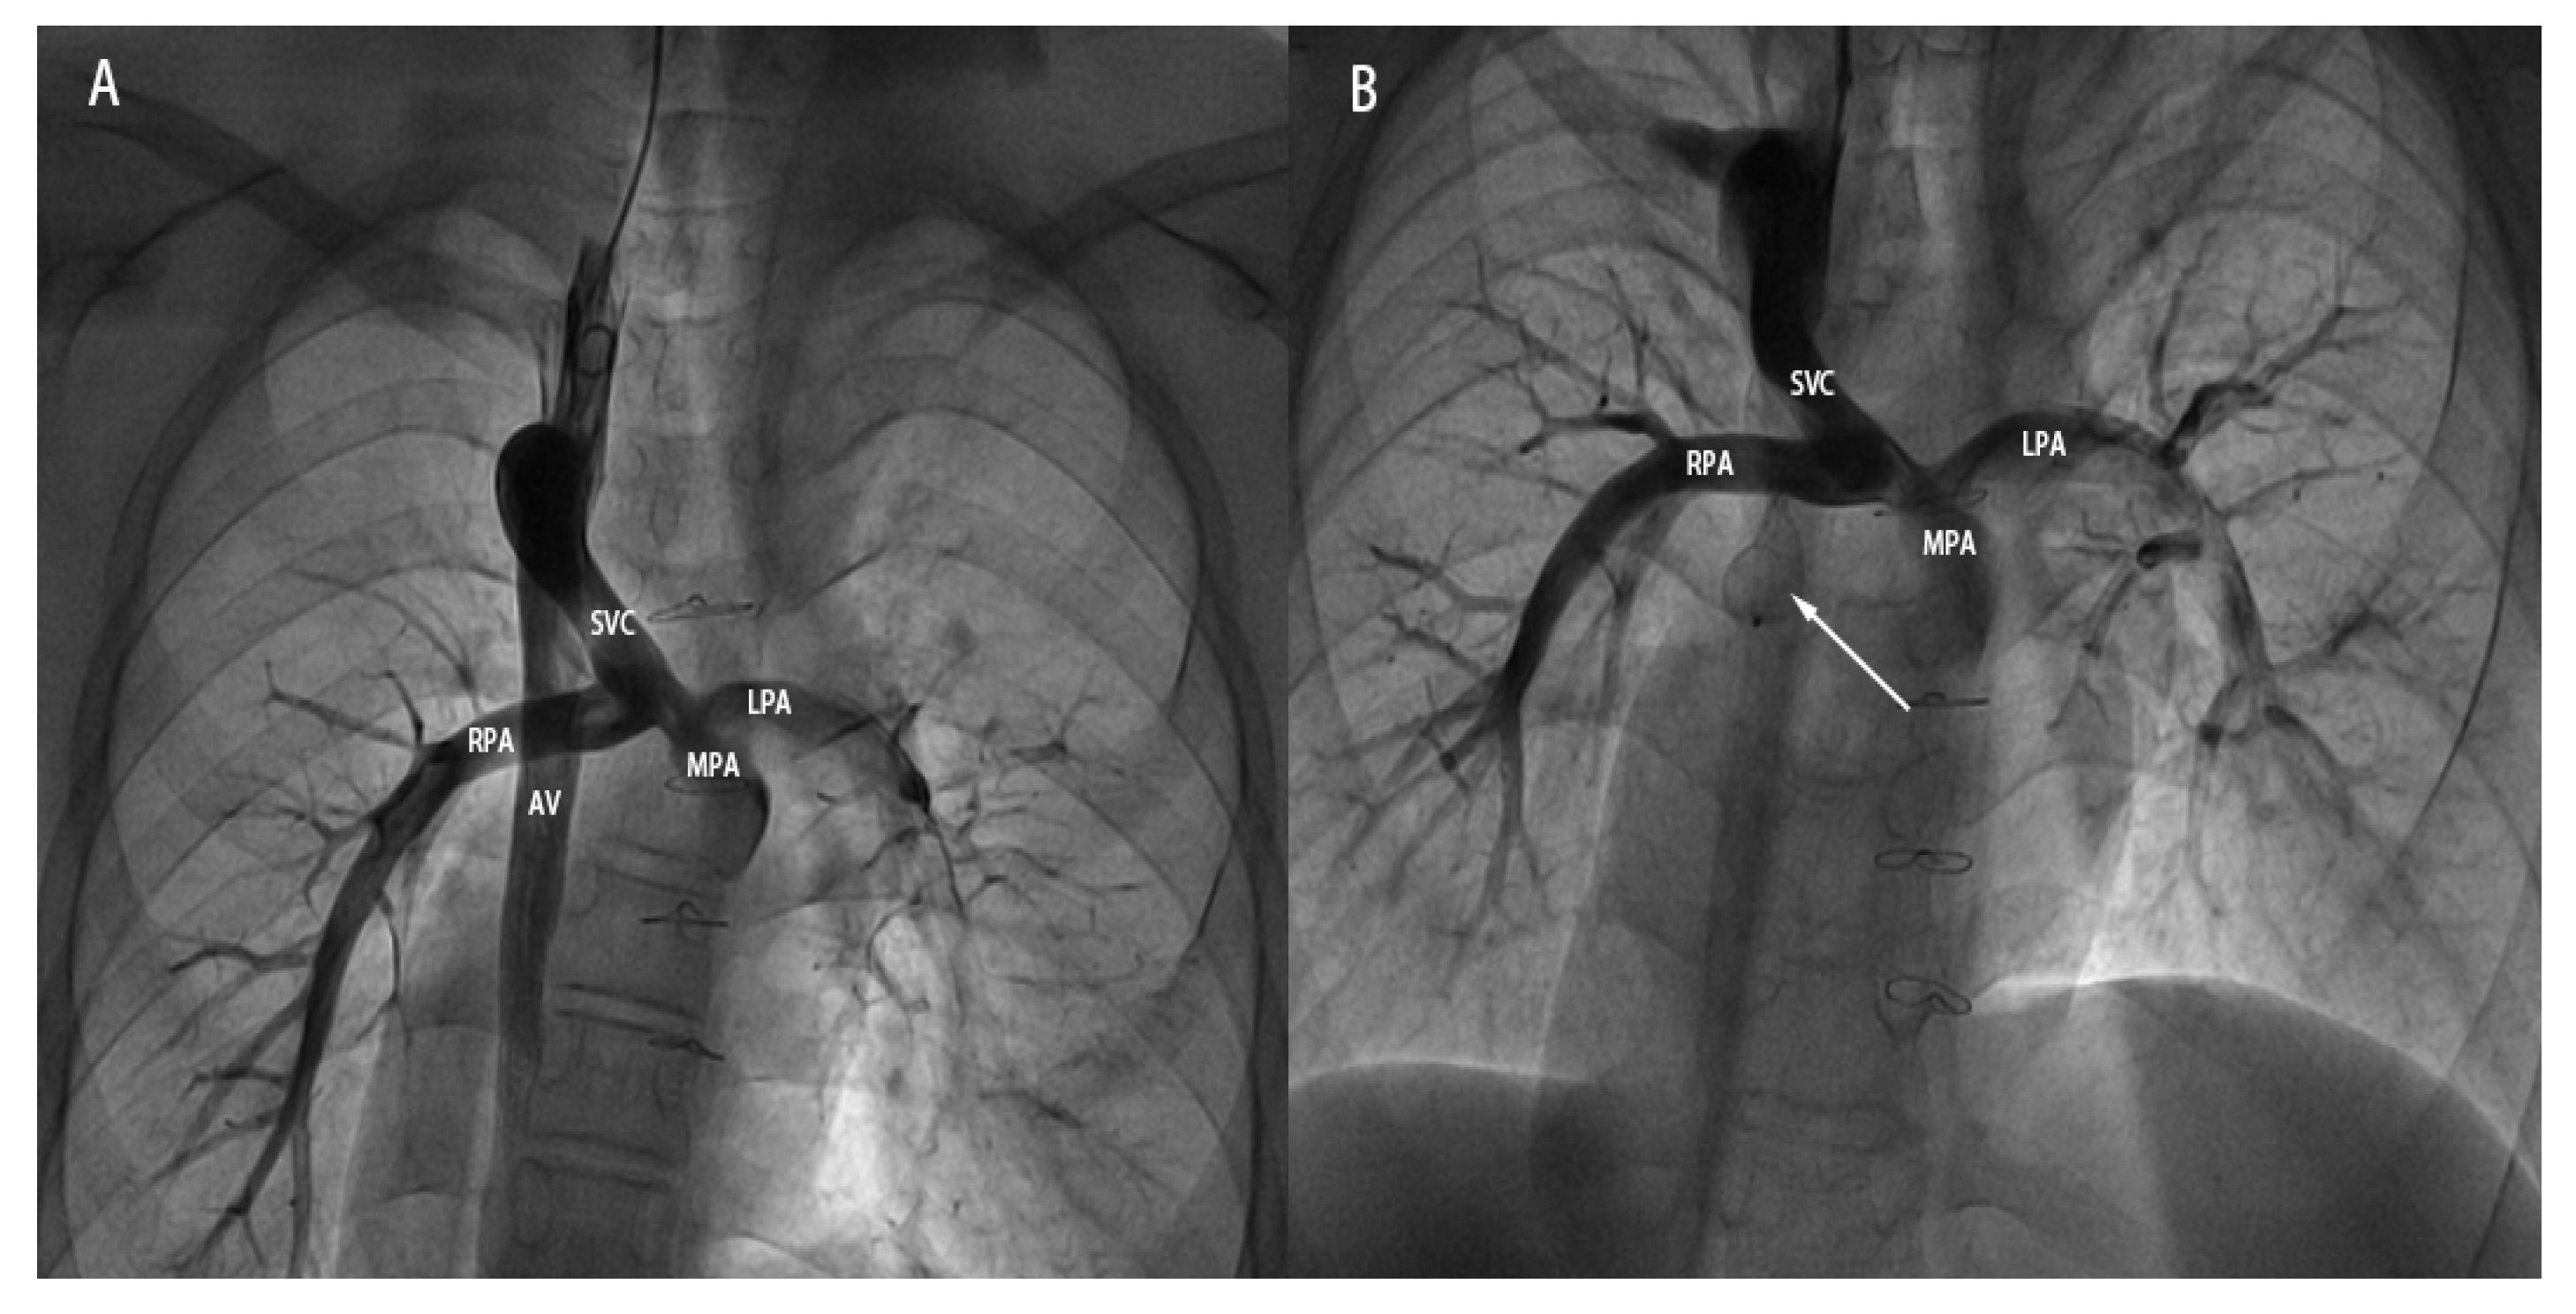

- (1)Case under local anesthesia: Vascular access was achieved via the right internal jugular vein. A 5-French pigtail catheter was introduced to perform angiography of the superior vena cava, pulmonary artery, and azygos vein (Fig. 2A). Through the same access route, a 16-mm atrial septal defect occluder was subsequently positioned and released to seal the proximal segment of the azygos vein. Post-deployment angiography verified complete occlusion, with no contrast filling observed in the mid- and distal portions of the vessel (Fig. 2B). The procedure concluded without any complications.

Figure 2: A 15-year-old male patient undergoing transcatheter closure of the dilated AV after BGP. (A): Pre-occlusion angiographic image showing the dilated AV originating from the SVC and draining downward. (B): Post-occlusion angiographic image showing the ASD occluder (indicated by the white arrow) in good shape and position, with no visualization of the middle and distal segments of the AV. SVC: superior vena cava; AV: azygos vein; MPA: main pulmonary artery; RPA: right pulmonary artery; LPA: left pulmonary artery.